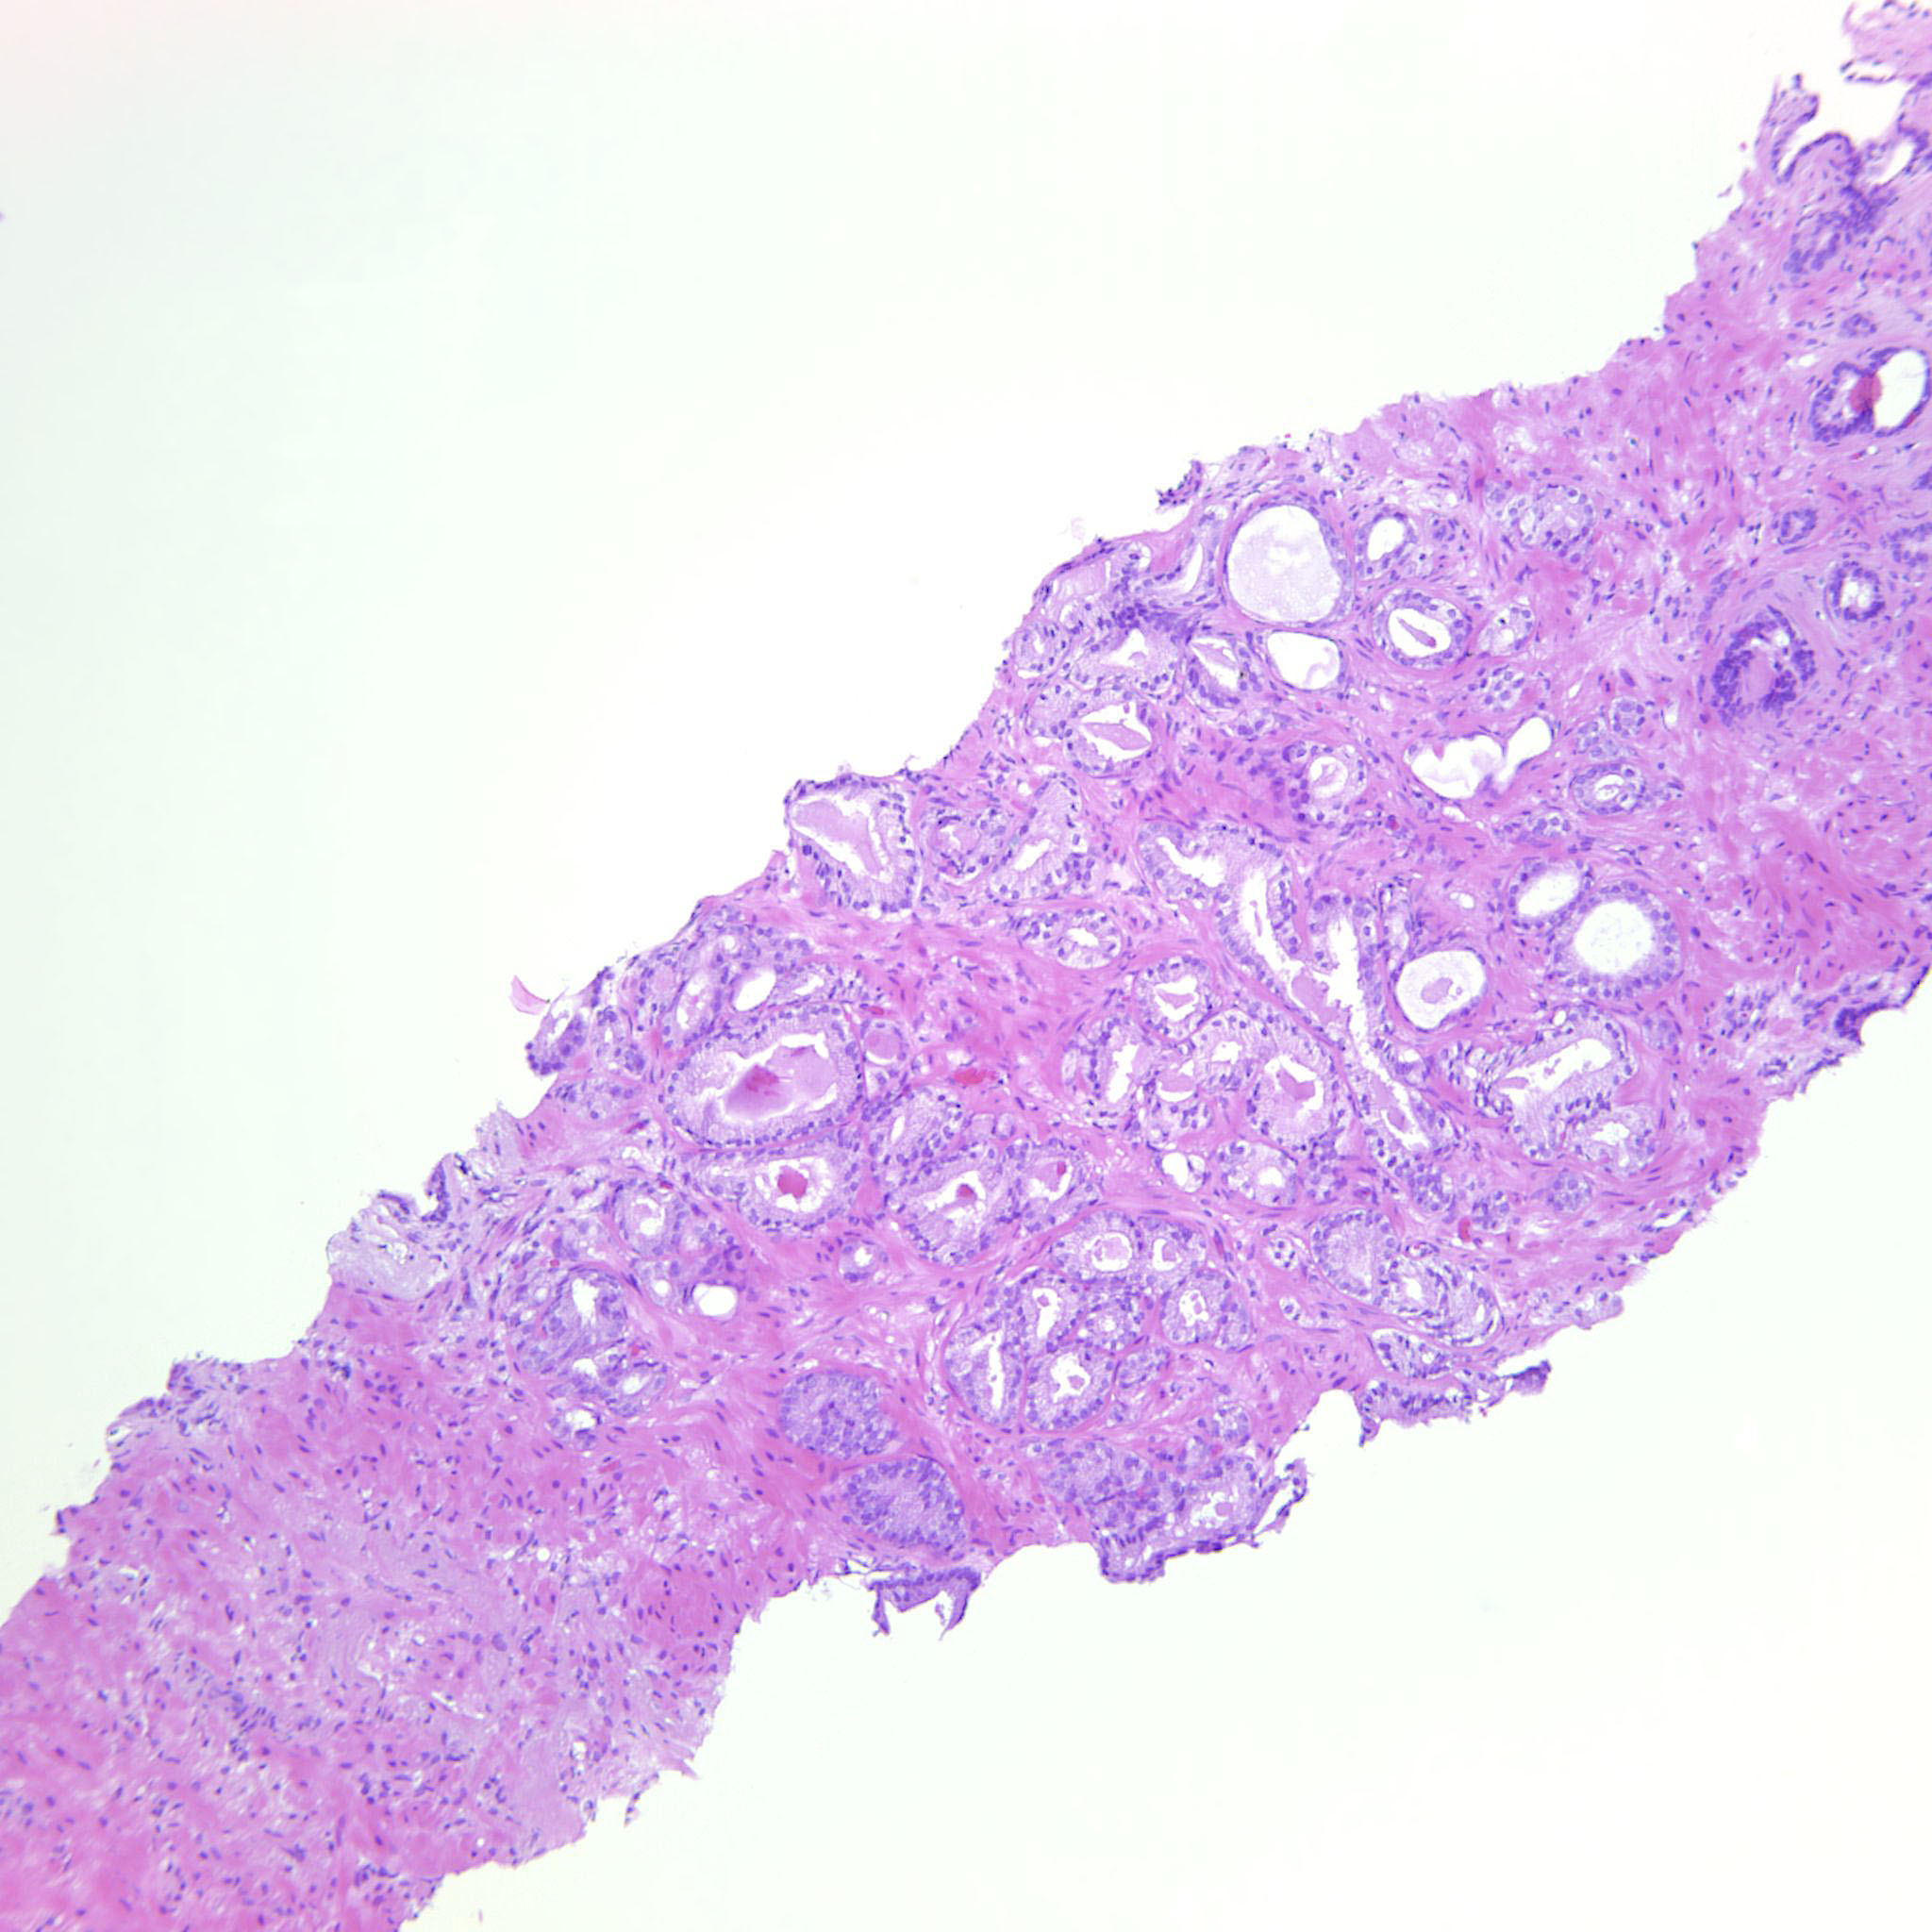

Prostate cancer grading

Case ID: 343